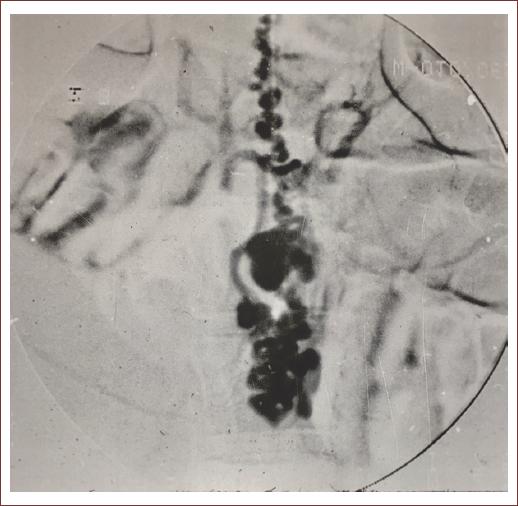

Imaging is an essential component in the diagnosis, management, and follow-up of patients with AVMs in the brain and spine. A wide variety of imaging modalities are available for its use, such as computed tomography (with its permutations: non-contrast, contrast enhanced, angiography perfusion, and myelography (Fig. 1) and magnetic resonance imaging (with its permutations: non-contrast, contrast enhanced, angiography, and myelography (Fig. 2). Although advances in this noninvasive imaging, digital subtraction angiography continues to be the gold standard for diagnosing and characterizing the detailed anatomic localization, arteriovenous transit, and venous drainage patterns of sAVMs29,33,38.

In sAVM, spinal angiography demonstrates a tangle of vessels at the level of the spinal cord parenchyma (Fig. 3). After delineation of the lesion, the neighboring vessels should be studied to identify potential feeders and to evaluate the effect of the lesion on the spinal cord. Anteroposterior angiography should be performed to identify feeding vessels and their origin from the anterior or posterior spinal artery (if any). Mass effect can distort the midline structures on frontal projection angiography and in this situation, the lateral projection angiography may help to delineate angioarchitecture. Three-dimensional angiography may help to define the relationship between the vascular malformations, bony structures, and the spinal cord. During the selective injection, contrast reflux into the lesion helps to identify the contributing feeders immediately above and below and is critical for planning endovascular treatment39,40.